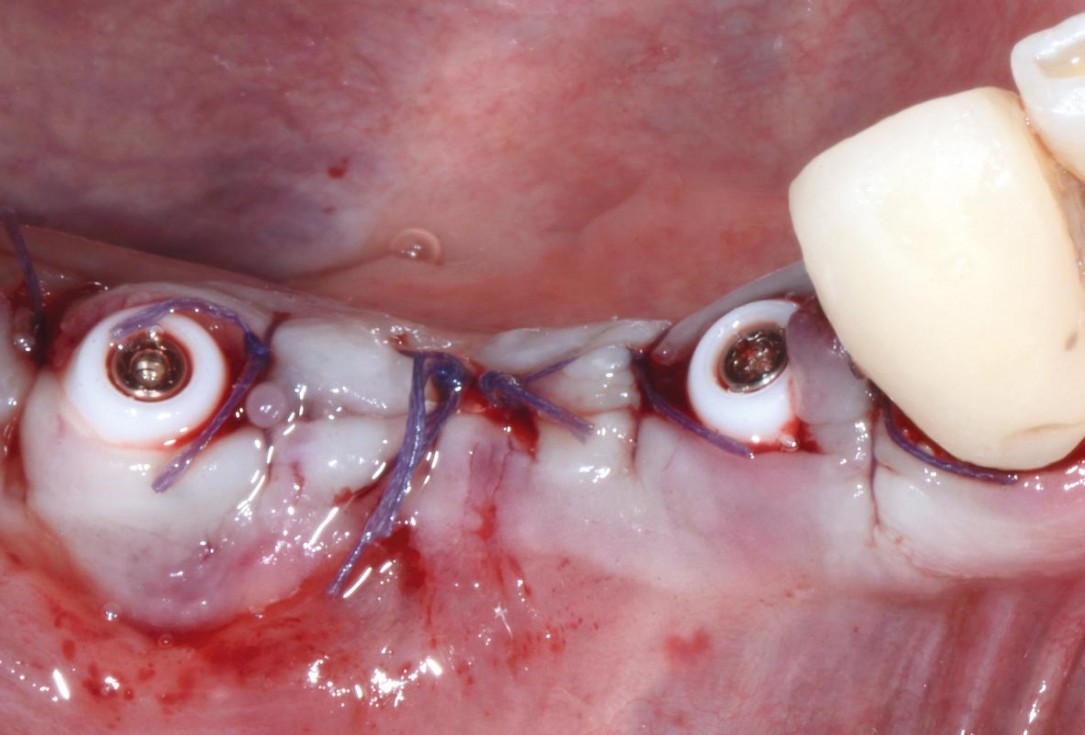

Multiple socket preservation in the mandibular with collacone® max – Dr. D. Jelušić